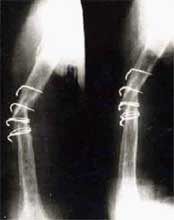

肱骨骨折,3次钢板和钢丝固定后失败。改用带锁髓内钉固定,4个月后骨折愈合。